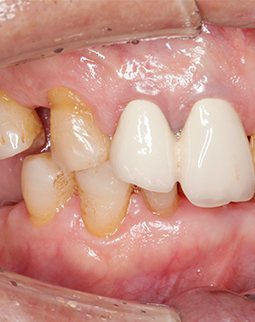

过去十天了,今天去拆线,然后歇上一段时间,我的手术创口比较多,难免要缝合。种植体重新拍摄了CT,植入良好,医生今天给我检查,种植牙术后并没有肿胀,恢复的还算不错,看来我老骥伏枥,体质还不错,也感谢医生种牙技术的高超,种植体都是微创的手术,种植牙的创口减小了,种植牙术后就更容易恢复了。

在我缺牙第一颗的时候,我就因为价格选择了活动牙。现在,我因为一副活动牙,逐渐损失了七颗好牙。人生啊,成佛成魔一念间。在深圳做种植牙的费用没有比其他城市贵多少,相反,我遇到了好的医院和医生,他们还给我少用了两颗种植体,帮我节省了种牙的费用。今天是我种好牙的第二天,因为口内植骨了,有点肿胀,麻药退了之后,我吃了医生开的消炎药,正常的服用温凉流食,按医嘱漱口,医生和客服工作人员都在给我贴心的回访,我感觉到很放心。

术后第10天